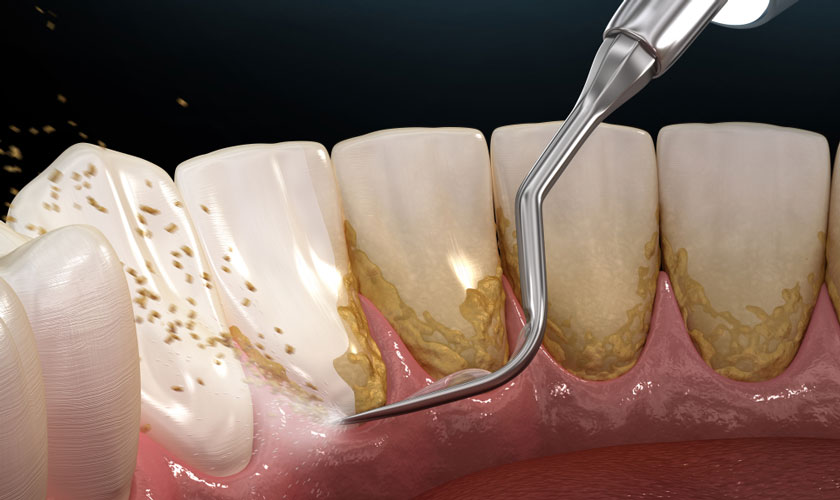

Vôi răng

Mảng bám thức ăn thừa lâu ngày sẽ bị vôi hóa bởi các khoáng chất có trong nước bọt, hình thành vôi răng. Vôi răng là môi trường lý tưởng của các loại vi khuẩn gây hại trú ngụ, vi khuẩn sẽ tấn công và làm tăng nguy cơ mắc các bệnh lý răng miệng như sâu răng, viêm nướu…

Vôi răng có thể gây viêm nướu khi bị sâu răng

Trường hợp sâu răng bị sưng lợi, cách tốt nhất chính là tìm một phòng khám nha khoa gần nhất có chất lượng cao để thăm khá và điều trị. Nếu tình trạng chưa nghiêm trọng, Bác sĩ sẽ loại bỏ vôi răng để giảm sưng nướu, nạo phần răng sâu và phục hình bằng vật liệu trám răng. Vật liệt trám sẽ giúp bảo vệ răng, ngăn ngừa vi khuẩn tấn công, cải thiện ăn nhai và thẩm mỹ.